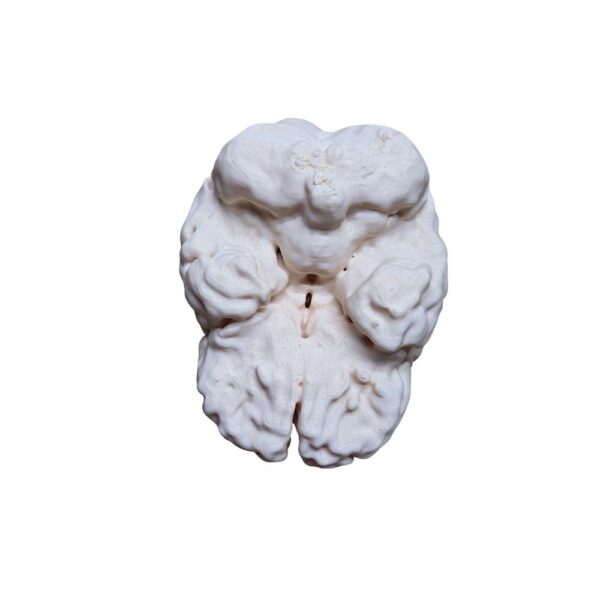

Obtenez une précision absolue avec cette réplique issue d’un scan 3D d’un véritable cerveau humain. Chaque circonvolution et structure est reproduite à l’identique de la réalité, offrant un outil d’étude et de référence d’un réalisme inégalé pour les passionnés et professionnels.

| Cerveau Humain Anatomique (Scan Réel) – Réplique Haute Fidélité | 1 11900 د.ج |